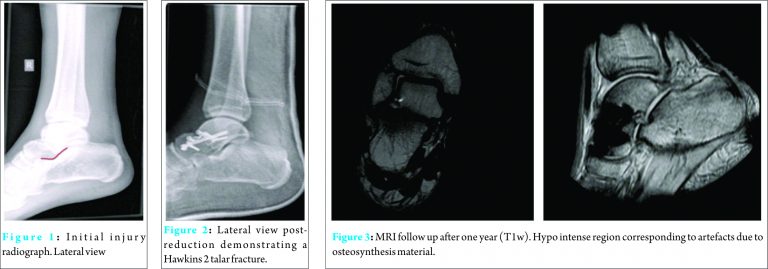

A 31-year-old patient who had a high impact trauma (car against a tree)was diagnosed with a pelvic ring fracture, a Hawkins II talar neck fracture of the right foot (Fig. 1) and a MTP [2,3,4] fracture of the left foot. Assessment by Advanced Trauma Life Support survey showed no additional injuries. There was no distal neurovascular deficit and no evidence of compartment syndrome. The talus fracture was initially treated by casting (8 days), followed by an open reduction (bilateral approach) and internal fixation (ORIF) by plate and screw osteosynthesis and cannulated screws (Fig. 2). After 10 days of hospitalization, the patient was signed up for intensive rehabilitation at a specialized unit. Rehabilitation comprised of early weight bearing, based on body awareness technique, mobilizing according to pain, and hydrotherapy. The recovery was surprisingly fast and within 7 weeks postoperatively, the patient could mobilize completely unaided and was even able to run (see video). At one year follow-up, patient did not experience any pain or functional disabilities. Follow-up X-ray did not demonstrate any mechanical failure and an MRI scan one year after surgery showed complete bone healing without signs of avascular necrosis.